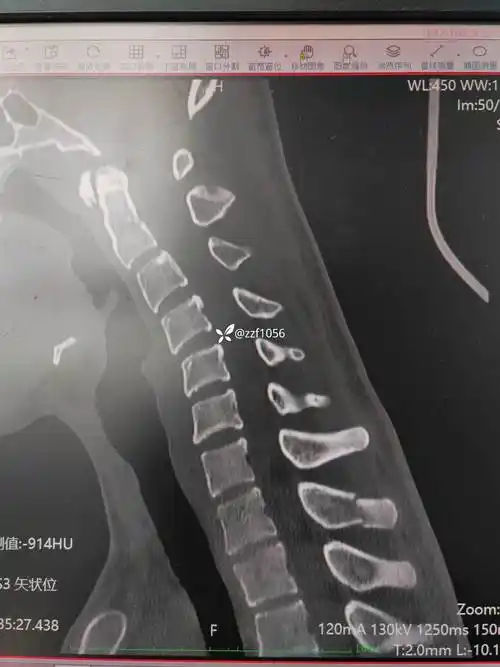

胸椎腰椎压缩性骨折

一位39岁的安先生不慎被重物砸伤,导致全身多发伤,胸椎骨折导致他当场

胸椎骨折